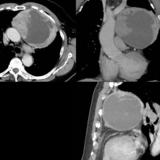

Case 9 Thymoma CT

Date: 04/04/2010

Views: 3594